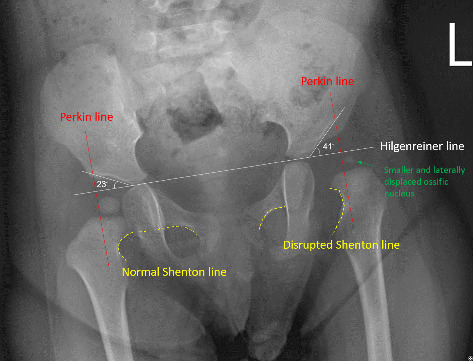

背景:迟发性髋关节发育不良(DDH)的诊断——定义为在8周龄后通过体格检查、超声或x线检查发现——发生在约0.14%-0.26%的婴儿中。本病例报告强调了延迟DDH诊断的挑战和物理治疗在康复中的作用。病例报告:患者为亚洲第一胎女性,妊娠40周顺产。她的早期病史包括左肌性斜颈、不对称哭脸综合征和喉软化。父母观察到不对称的臀沟,但3个月前的早期体检显示Barlow和Ortolani试验阴性,髋关节活动范围正常,无运动障碍。因此,由于身体检查结果阴性,缺乏典型的表现和体征,以及缺乏通常需要进一步影像学评估的主要危险因素,因此在婴儿早期超声成像被认为是不必要的。11个月时,负重减轻和腿长不一致的迹象导致x线检查,显示左DDH伴半脱位。治疗包括闭合复位、14周Spica石膏、14个月外展支具和物理治疗。铸造后,患者出现髋关节僵硬、活动受限和肌肉无力。物理治疗的重点是恢复运动,同时确保关节的稳定性。通过每周一次的治疗,患者取得了显著的进步,在19个月时实现了独立行走。随访x线片显示髋臼指数逐渐改善,在6岁零9个月时接近正常发育。结论:本病例强调了DDH早期检测的挑战,延迟诊断的后果,以及物理治疗在DDH患儿术后恢复和功能发展中的重要作用。

Background: Delayed diagnosis of developmental dysplasia of the hip (DDH)-defined as detection after 8 weeks of age using physical examination, ultrasound, or X-ray-occurs in approximately 0.14%-0.26% of infants. This case report highlights the challenges of delayed DDH diagnosis and the role of physical therapy in rehabilitation. Case Report: The patient, a firstborn Asian female, was born vaginally at 40 weeks gestation. Her early medical history included left muscular torticollis, asymmetric crying faces syndrome, and laryngomalacia. Parents observed asymmetric gluteal folds, but early physical examinations before 3 months showed negative Barlow and Ortolani tests, normal hip range of motion, and no motor impairments. Thus, ultrasound imaging was not deemed necessary in early infancy due to negative physical exam findings, the absence of classic presentations and signs, and a lack of major risk factors that would typically warrant further imaging evaluation. At 11 months, signs of reduced weight bearing and leg length discrepancy led to radiographic evaluation, revealing left DDH with subluxation. Treatment included closed reduction, 14 weeks in a Spica cast, 14 months of abduction bracing, and physical therapy. Following casting, the patient experienced hip stiffness, limited mobility, and muscle weakness. Physical therapy focused on restoring movement while ensuring joint stability. With weekly sessions, the patient showed significant progress, achieving independent walking at 19 months. Follow-up radiographs demonstrated gradual acetabular index improvement, approaching normal development by age 6 years and 9 months. Conclusion: This case highlights the challenges of early DDH detection, the consequences of delayed diagnosis, and the vital role of physical therapy in postoperative recovery and functional development of children with DDH.